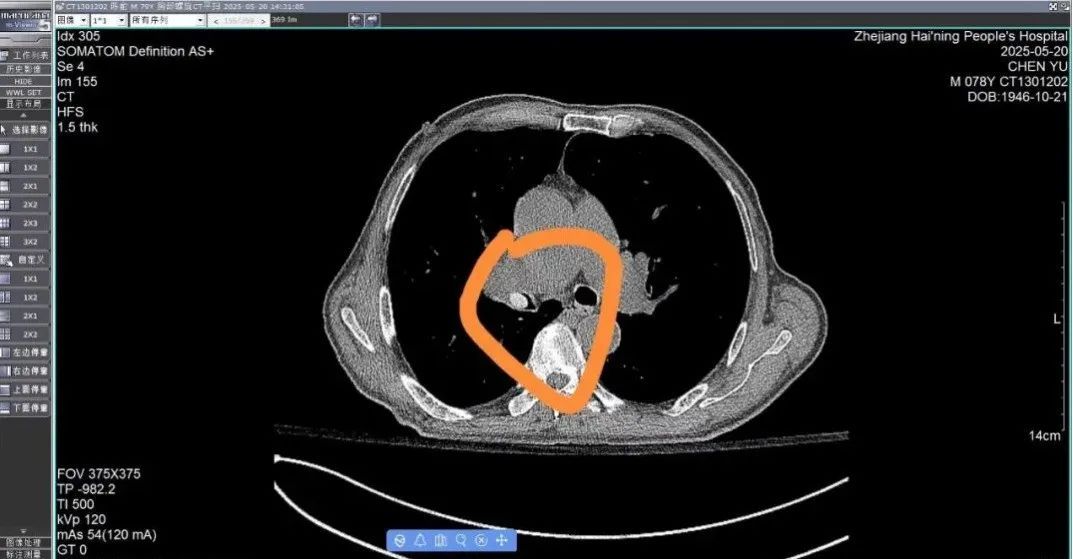

陈大爷因慢性阻塞性肺疾病反复住院,半月前出院后,他的病情一直很稳定。但2天前,他突然出现胸闷气促、喉部喘鸣、有窒息感、不能平卧等症状,随即来海宁市人民医院就诊。查CT发现,一个新出现的高密度类圆形结节卡在右侧主气管。